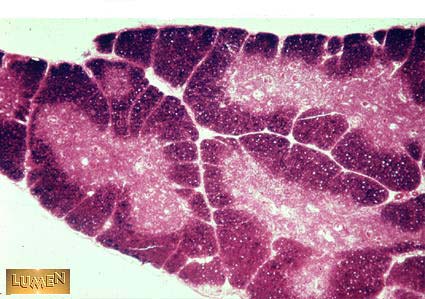

What organ is this? Be Specific!

Young Thymus